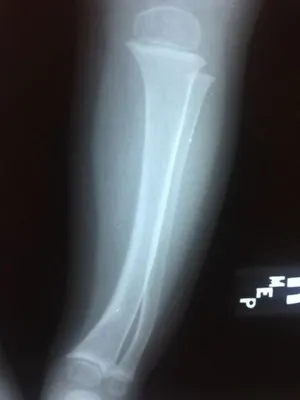

Xrays of Bow Legs in toddler (Below)

Knock knee position is demonstrated (left), and the bowleg position is also pictured (right).